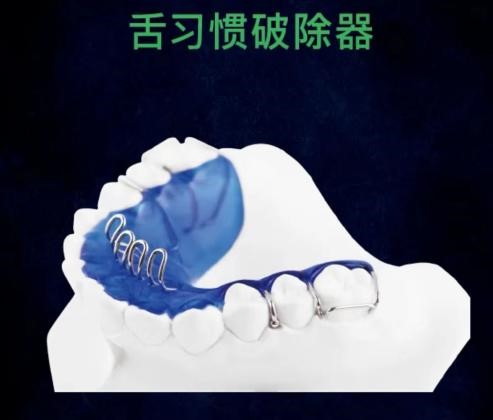

3.使用破除不良习惯矫正器。必要时可做腭刺、腭网或腭屏来破除不良舌习惯。